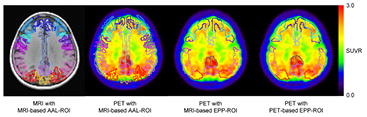

Table 2 shows the SUVR obtained by three methods. The higher SUVR was obtained with EPP-ROI compared with the AAL-ROI when MRI-based normalization was used. On the other hand, the SUVR were almost the same between MRI-based and PET-based methods as long as EPP-ROI was employed. Figure 6 shows the representative ROI setting of the three methods on a PiB positive subject. MRI-based AAL-ROI protruded from the cortex while the EPP-ROI was localized over the PiB accumulative cortical areas. In PET-based normalization process, the NCC value chose the 'correct' template corresponding to the actual visual classification for all negative images. For the positive images, accordance was found for 87% of the subjects (20/23 cases).

Figure 6. MRI and PET superimposed with three types of ROI for a representative 'positive' subject. MRI-based AAL-ROI protruded from cortical surface due to gray matter segmentation error. On the other hand, the EPP-ROI was localized within the cortical areas.